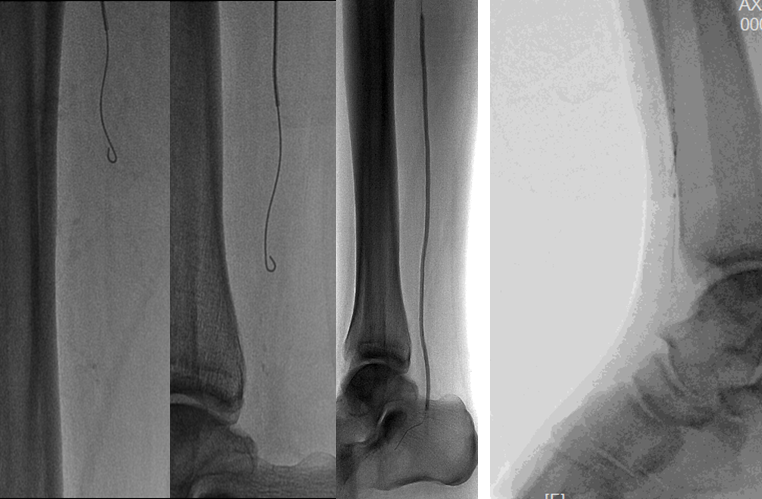

BTK病变多为长段、弥漫、钙化、CTO,多累及踝下(BTA)

病变常为单个或多个CTO组合,总长度可达20cm;

部分患者存在踝上交通动脉或完整的踝下足底弓,为逆向开通提供可能。